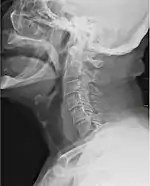

Горло отображается на рентгене как тёмная полоса у передней части позвоночника.